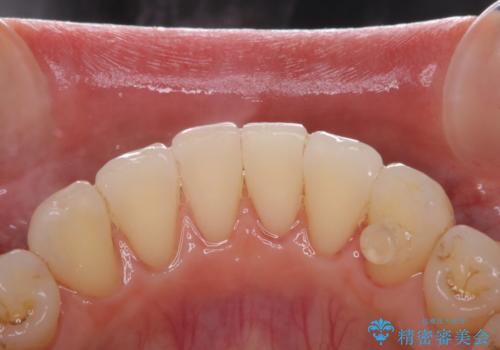

30代男性 PMTCで歯石取り

担当医 歯科衛生士